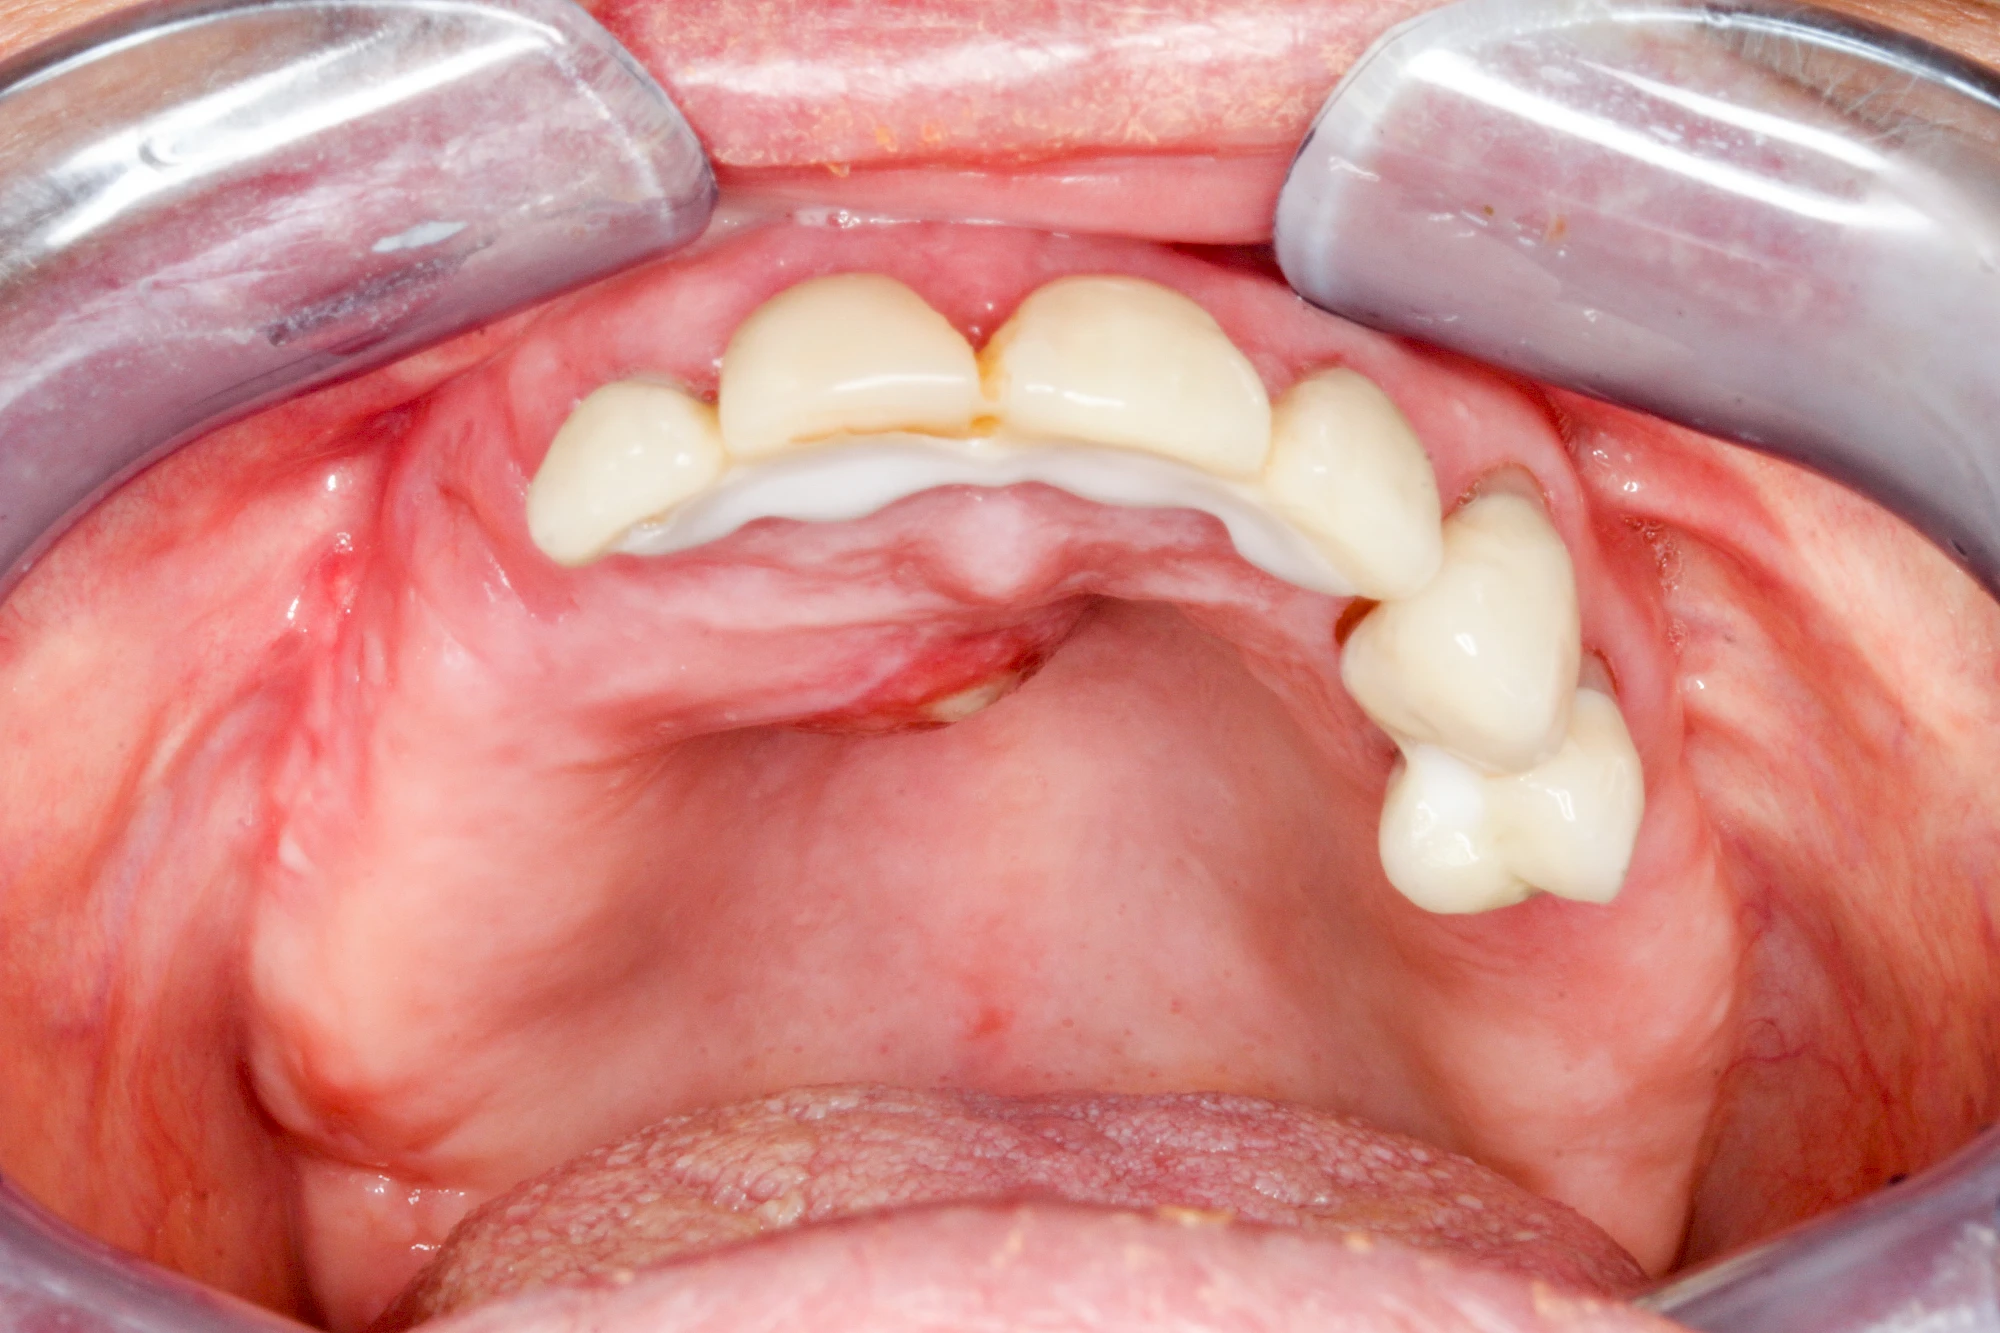

Diese Vermehrung von Bindegewebe in einem frei gewordenen Raum ist eine Sonderform der Anpassungsreaktion menschlicher Zellen und wird als Vakatwucherung bezeichnet.

Früher wurden im Unterkiefer mitunter Brücken zum Ersatz fehlender Zähne als sogenannte "Schwebebrücken" gestaltet. Die Idee dabei war, dass man die Brücke insgesamt besser reinigen kann. Allerdings war das für die Patienten mitunter irritierend für die Zunge und vor allem beim Essen gewöhnungsbedürftig. Teilweise haben sich hier reaktiv Vakatwucherungen der Kieferkammschleimhaut gebildet und den Raum unter der Brücke wieder verschlossen.